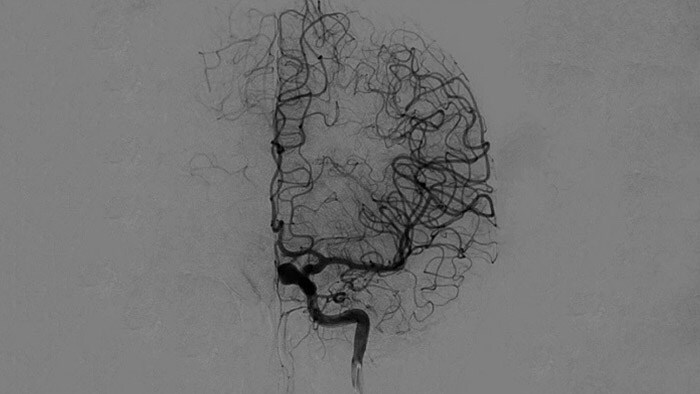

Bevestig dat de behandeling is geslaagd

Met hoogwaardige DSA-visualisaties kunt u beoordelen of u het volledige stolsel hebt verwijderd en of er stukjes stolsel distaal in de hersenen zijn verspreid. U kunt het herstel van de bloedstroom naar de penumbra controleren en eventuele periprocedurele bloedingen vaststellen.